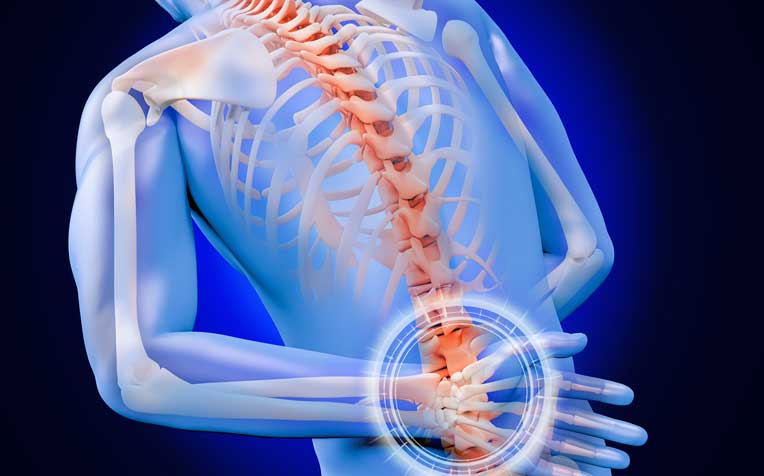

Espondilitis Anquilosante

La espondilitis anquilosante (E.A.) también llamada Morbus Bechterew, Mal de Bechterew-Strümpell-Marie, Espondilitis reumática y Espondilitis anquilopoyética.